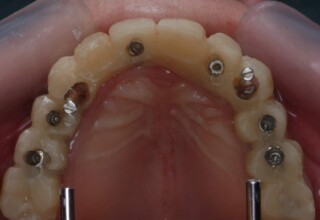

Ολική Στοματική Αποκατάσταση σε Εμφυτεύματα με διαφορετική προσέγγιση στην Άνω και Κάτω Γνάθο

Κάτω γνάθος: εξαγωγές, άμεση τοποθέτηση εμφυτευμάτων και άμεση φόρτιση(την ίδια ημέρα) με προσωρινή γέφυρα

Άνω γνάθος: σταδιακές εξαγωγές, σταδιακή τοποθέτηση εμφυτευμάτων και σταδιακή ενσωμάτωση τους στην προσωρινή γέφυρα ώστε η ασθενής να μην μείνει ούτε μια ημέρα χωρίς αποκατάσταση. Στόχος η συνεχής λειτουργική και αισθητική αποκατάσταση της ασθενούς χωρίς άμεση φόρτιση των εμφυτευμάτων λόγω ανατομικών ιδιαιτεροτήτων.

Χρησιμοποιήθηκαν παλαιές χαμογελαστές φωτογραφίες της ασθενούς γιατί είχε χαθεί τελείως το φυσικό σχήμα των δοντιών εξαιτίας των πολλαπλών προσθετικών προσπαθειών που είχαν γίνει στο παρελθόν. Μεταφέρθηκε στην προσωρινή γέφυρα η σχέση των φυσικών δοντιών μεταξύ τους άλλα και με τα χείλη. Δοκιμάστηκε η φώνηση και η μάσηση με δυο διαφορετικές προσωρινές άνω γέφυρες και εκτιμήθηκε η αισθητική απόδοση τους. Αφού επιτεύχθηκαν σε βαθμό ικανοποιητικό η φώνηση και η αισθητική εμφάνιση της οδοντοφυΐας, η προσωρινή αποκατάσταση χρησιμοποιήθηκε ως οδηγός για την τελική.